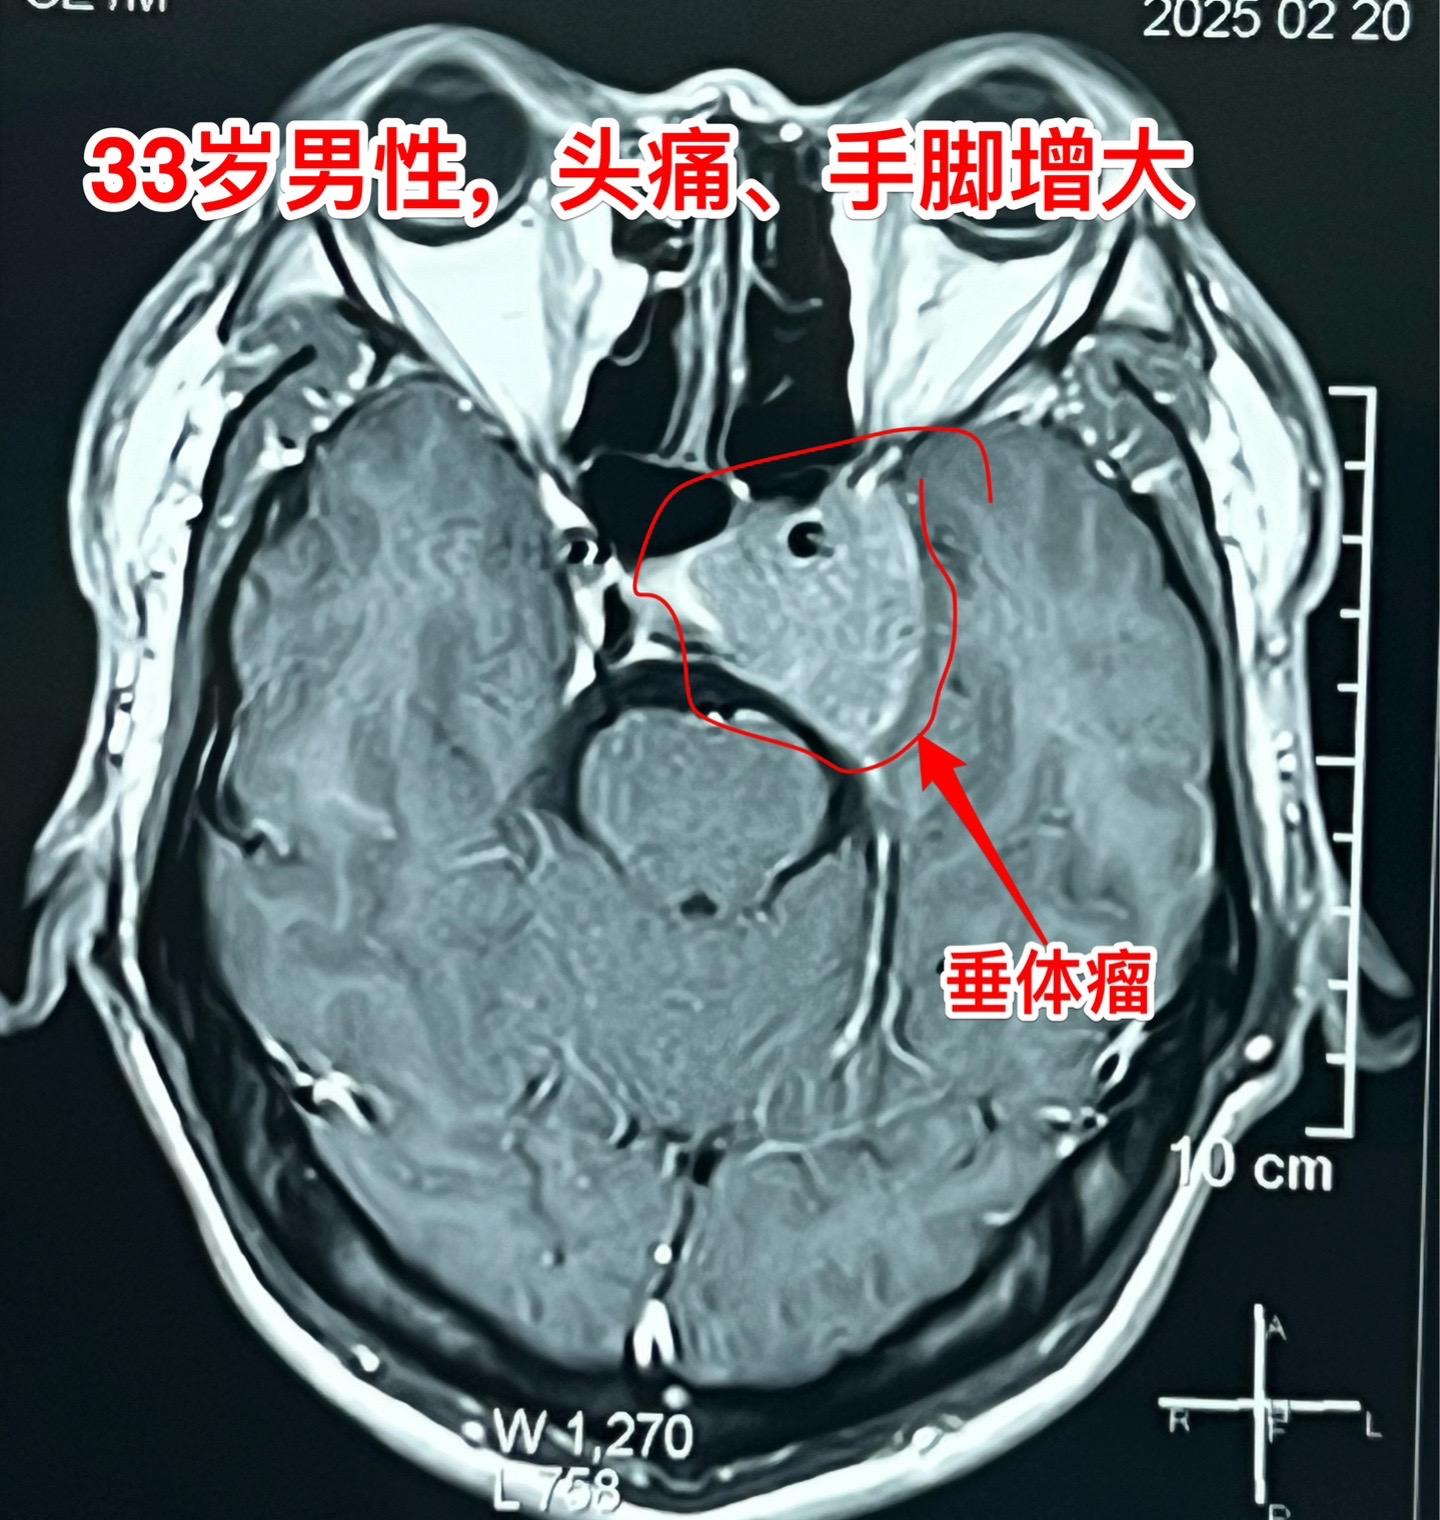

走来街上就能确诊的疾病:垂体生长激素腺瘤。有的疾病经过医生多年排查都不能确诊。 有的疾病走在街上就可以确诊! 这绝对不是忽悠! 垂体生长激素腺瘤造成的肢端肥大症,病人走在街上医生看一眼可以确诊!因为这个病有十分显著的特征! 肢端肥大面容一般伴有手脚增大(在成年后鞋号还在增大!)。今天说的这个病人33岁男性,近四年经常感到头痛,鞋号从42码增长到44码。面容也有改变,鼻子变大、口唇增厚、眉弓处隆起。 抽血化验生长激素,结果几乎达